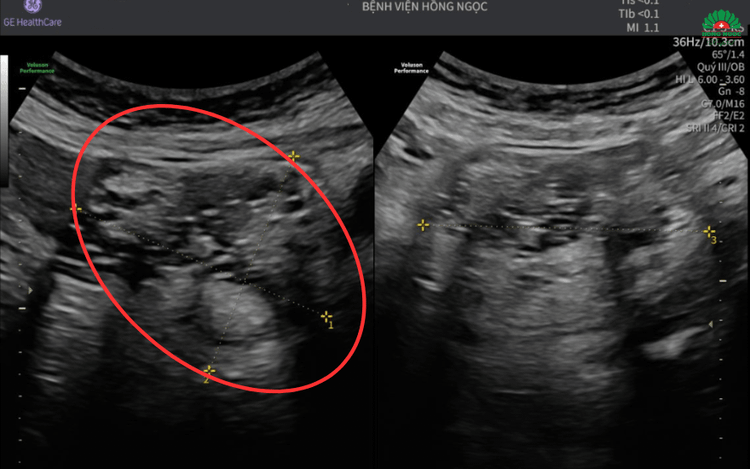

Tại đây, chị được chỉ định siêu âm và chụp MRI ổ bụng, kết quả cho thấy u buồng trứng kích thước hơn 7cm cùng hình ảnh mô đặc, mỡ, xương - gợi ý u quái trưởng thành. Để ngăn chặn biến chứng ảnh hưởng đến sức khỏe, các bác sĩ quyết định thực hiện phẫu thuật nội soi loại bỏ khối u cùng hai phần phụ.

Khối u buồng trứng kích thước hơn 7cm chèn ép các tạng xung quanh - Ảnh BVCC

“Mặc dù khối u có kích thước không quá lớn nhưng đã kéo cả tử cung và buồng trứng lên quá rốn, chèn vào bàng quang. Vì vậy, ê-kíp phẫu thuật phải hết sức tỉ mỉ để loại bỏ được toàn bộ khối u cùng các tổ chức bất thường, đồng thời không làm ảnh hưởng đến các cơ quan lân cận”, ThS.BS Nguyễn Thị Thùy - Phó Trưởng khoa Sản Phụ khoa, Bệnh viện Đa khoa Hồng Ngọc Phúc Trường Minh - bác sĩ trực tiếp điều trị cho bệnh nhân T. chia sẻ.